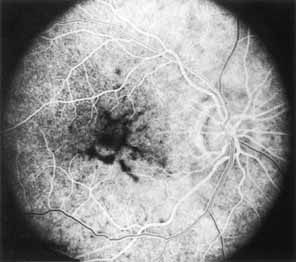

Although there is no reported genetic heterogeneity, there is wide phenotypic variation within the disorder. The major finding within the macula is a classic radial cystic maculopathy. Although retinal signs have been described in infants as young as 3 months, foveal schisis may be difficult to detect, leading to underdiagnosis. The diagnosis is usually not made until the affected male reaches school age (4 to 8 years of age) and encounters visual problems secondary to foveal involvement. Typical foveal schisis findings have been reported in 68% to 100% of eyes within various series.37,38 Foveal schisis is the only finding in about half the cases. It is characterized by the presence of radiate perifoveal microcysts located in the nerve fiber layer (Fig. 1) with radiate plications of the overlying internal limiting membrane that are seen especially well on monochromatic (red-free) photography (Fig. 2). The microcystoid change may slowly progress to form a macular cyst or hole. Foveal schisis has been reported in association with Goldmann-Favre vitreotapetoretinal dystrophy and rarely may be seen in rod-cone dystrophy or as an autosomal dominant or recessive condition.39–43